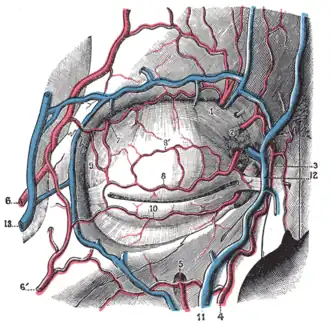

Blood vessels of the eyelids, front view. 1, supraorbital artery and supraorbital vein; 2, nasal artery; 3, angular artery, the terminal branch of 4, the facial artery; 5, suborbital artery; 6, anterior branch of the superficial temporal artery; 6’, malar branch of the transverse artery of the face; 7, lacrimal artery; 8, superior palpebral artery with 8’, its external arch; 9, anastomoses of the superior palpebral with the superficial temporal and lacrimal; 10, inferior palpebral artery; 11, facial vein; 12, angular vein; 13, branch of the superficial temporal vein. | |